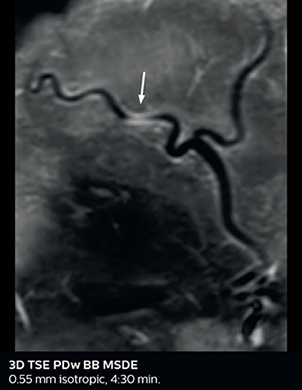

So, what is the actual impact of having more information and more diagnostic confidence? According to Dr. Savatovsky, “One of the indications I’ve seen where using Elition is most impactful is in patients with suspected giant cell arteritis. As an ophthalmologic hospital, we see many patients with suspected giant cell arteritis. Usually we were performing MRI to help us rule out an ischemic stroke, and to verify that the supra aortic vessels are undamaged. With Elition, we still do this, but now we can add on more detailed high-resolution black-blood sequences on superficial arteries. This provides us with high confidence levels for diagnosis of giant cell arteritis (GCA) and as a result, some patients are not sent for a biopsy anymore. A patient who has a normal MRI will not require a biopsy and can be discharged from the hospital in the same day. Before, such a patient would have to stay for about a week, just to find that their biopsy results were negative. We have at least three or four patients a week with suspected giant cell arteritis. For a great deal of these patients we can have a direct impact on their hospital stay.”

Giant cell arteritis

The 3D TSE T1w black blood MSDE sequence with fat suppression has an isotropic 0.8 mm voxel size and sagittal oblique and axial reformats are made. The images show superficial temporal artery thickening and peri-arterial fat infiltration. The 3D TSE PDw black blood MSDE with fat suppression has 0.55 mm isotropic voxels. The images shows focal involvement of the frontal branch of the superficial temporal artery.